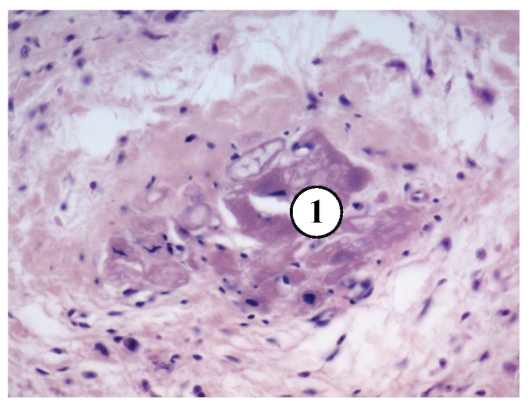

Межуточный миокардит: гистологические исследования